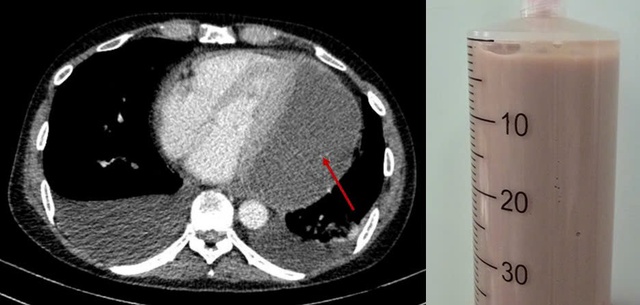

Chụp CT lồng ngực ghi nhận lớp dịch mủ chèn ép tim (mũi tên đỏ) và dịch mủ đặc rút ra được qua chọc dịch màng ngoài tim. Ảnh: BVCC.

"Đây là một ca chọc hút phức tạp và tiềm ẩn nhiều nguy cơ do khối mủ nằm ở vị trí khó tiếp cận, dịch đặc quánh. Tuy nhiên, các bác sĩ đã hút thành công 500ml mủ đặc, giảm nhanh áp lực lên tim", Trưởng khoa Phẫu thuật tim - Lồng ngực mạch máu cho biết.